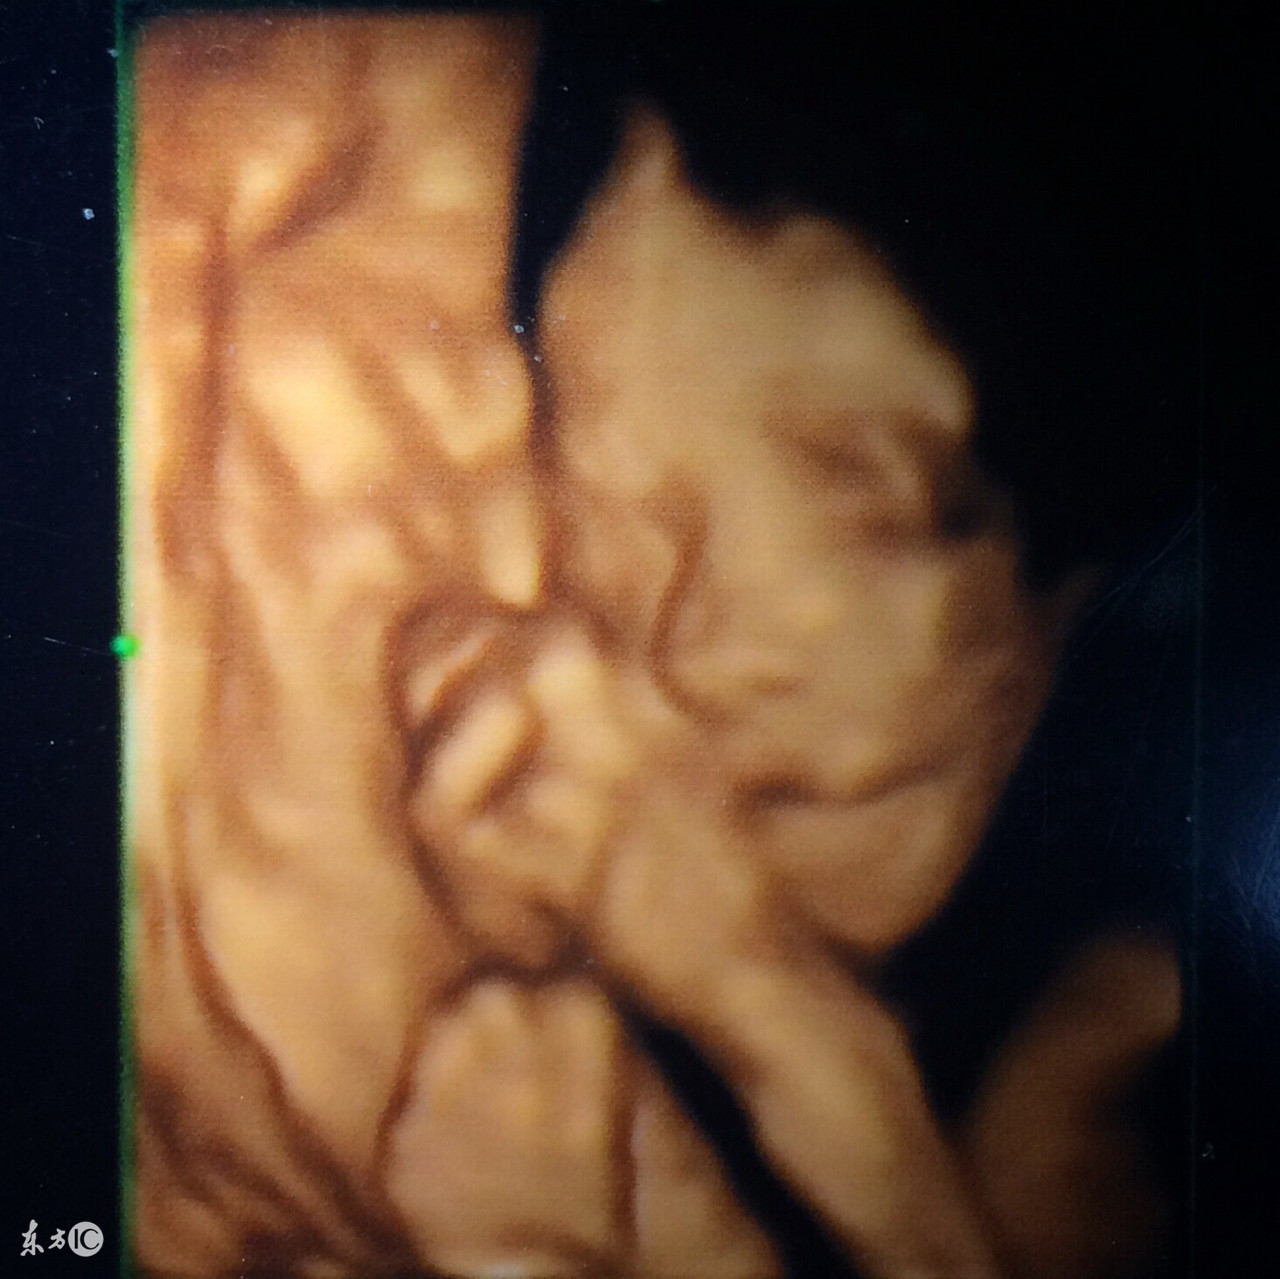

5、三维彩超:可能是土黄色,图片,静态,有排畸作用;

6、四维彩超:可能是土黄色,录像,动态,能够刻录成光盘,有排畸作用;

3、四维彩超

四维彩超也称大排畸检查,做四维彩超的最佳时间是在24-28周,这时宫内空间大,宝宝活动方便,回声比较小,图像会更加清楚。